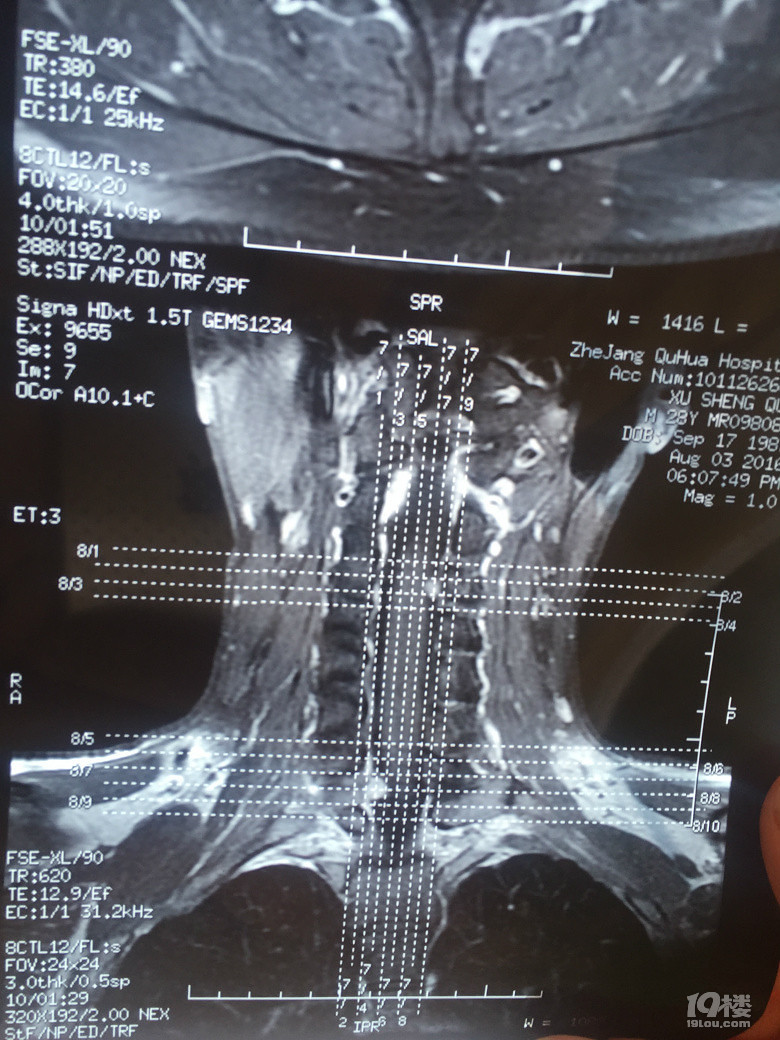

我要动手术了,求推荐【浙二医院脊柱肿瘤科】

我要动手术了,求推荐【浙二医院脊柱肿瘤科】

我要动手术了,求推荐【浙二医院脊柱肿瘤科】